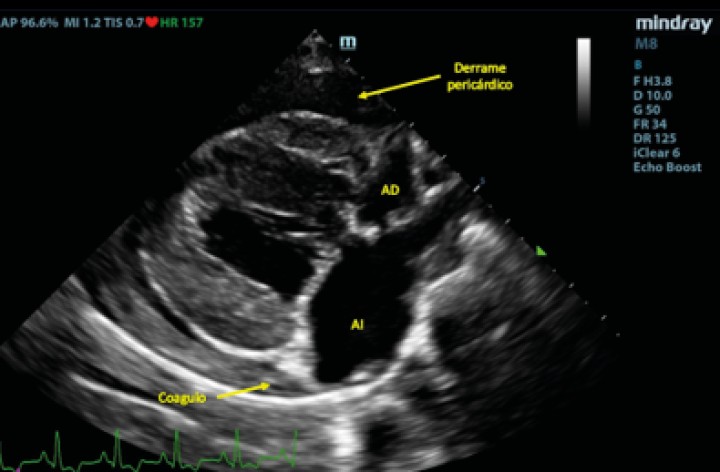

Posteriormente se evaluó al paciente mediante un examen TFAST, detectando derrame pericárdico y disminución del tamaño del AI (Fig. 4), como hallazgos diferentes a los observados en el examen realizado previo a la radiografía. La rápida respuesta por parte del equipo veterinario implicó que en este primer examen ecográfico tras el desvanecimiento del paciente no se había producido la formación del coágulo para taponar la fisura de la pared, observando flujo desde el AI hacia el saco pericárdico. Se realizaron exámenes TFAST seriados para evaluar la necesidad de realizar una pericardiocentesis al paciente durante la hora siguiente al episodio. En los exámenes seriados realizados no se observaron signos ecocardiográficos de taponamiento cardíaco, por lo que se decidió no realizar un vaciado del contenido pericárdico mediante pericardiocentesis[ Rush JE: Cardiac emergencies. En Rozanski EA and Rush JE (ed): Small Animal Emergency and Critical Care Medicine: A Colour Handbook, London, Manson Publishing, 2007; 52-56 , Kirby R: Cardiovascular case 79. En Kirby R (ed): Self-assessment color review of small animal emergency & critical care medicine, London, Veterinary Press, 1998; 67-71. ] y se optó por un tratamiento de soporte basado en oxigenoterapia y fluidoterapia, buscando mantener un correcto gasto cardíaco sin aumentar en exceso la presión sistólica del paciente, lo que podría producir un aumento del sangrado a través del defecto de la pared atrial, así como una dosis única de pimobendán (Vetmedin, Boehringer Ingelheim, Rhein) por vía intravenosa a 0,15 mg/kg. A los 15 minutos tras el episodio de desvanecimiento, se observó la presencia de una estructura hiperecoica en la pared del AI en el examen ecográfico, compatible con la formación de un coágulo (Fig. 5).

<p>Examen TFAST tras la rotura del atrio izquierdo donde podemos observar un corte transversal del corazón a la altura de los músculos papilares de ventrículo izquierdo. Se puede observar la presencia de derrame pericárdico. VD: ventrículo derecho; VI: ventrículo izquierdo.</p>

Figura 4

Examen TFAST tras la rotura del atrio izquierdo donde podemos observar un corte transversal del corazón a la altura de los músculos papilares de ventrículo izquierdo. Se puede observar la presencia de derrame pericárdico. VD: ventrículo derecho; VI: ventrículo izquierdo.

<p>Corte paraesternal derecho 4 cámaras tras la rotura del atrio izquierdo. Se puede observar la formación de una estructura compatible con un coágulo dentro del saco pericárdico. AD: atrio derecho; AI: atrio izquierdo.</p>

Figura 5

Corte paraesternal derecho 4 cámaras tras la rotura del atrio izquierdo. Se puede observar la formación de una estructura compatible con un coágulo dentro del saco pericárdico. AD: atrio derecho; AI: atrio izquierdo.